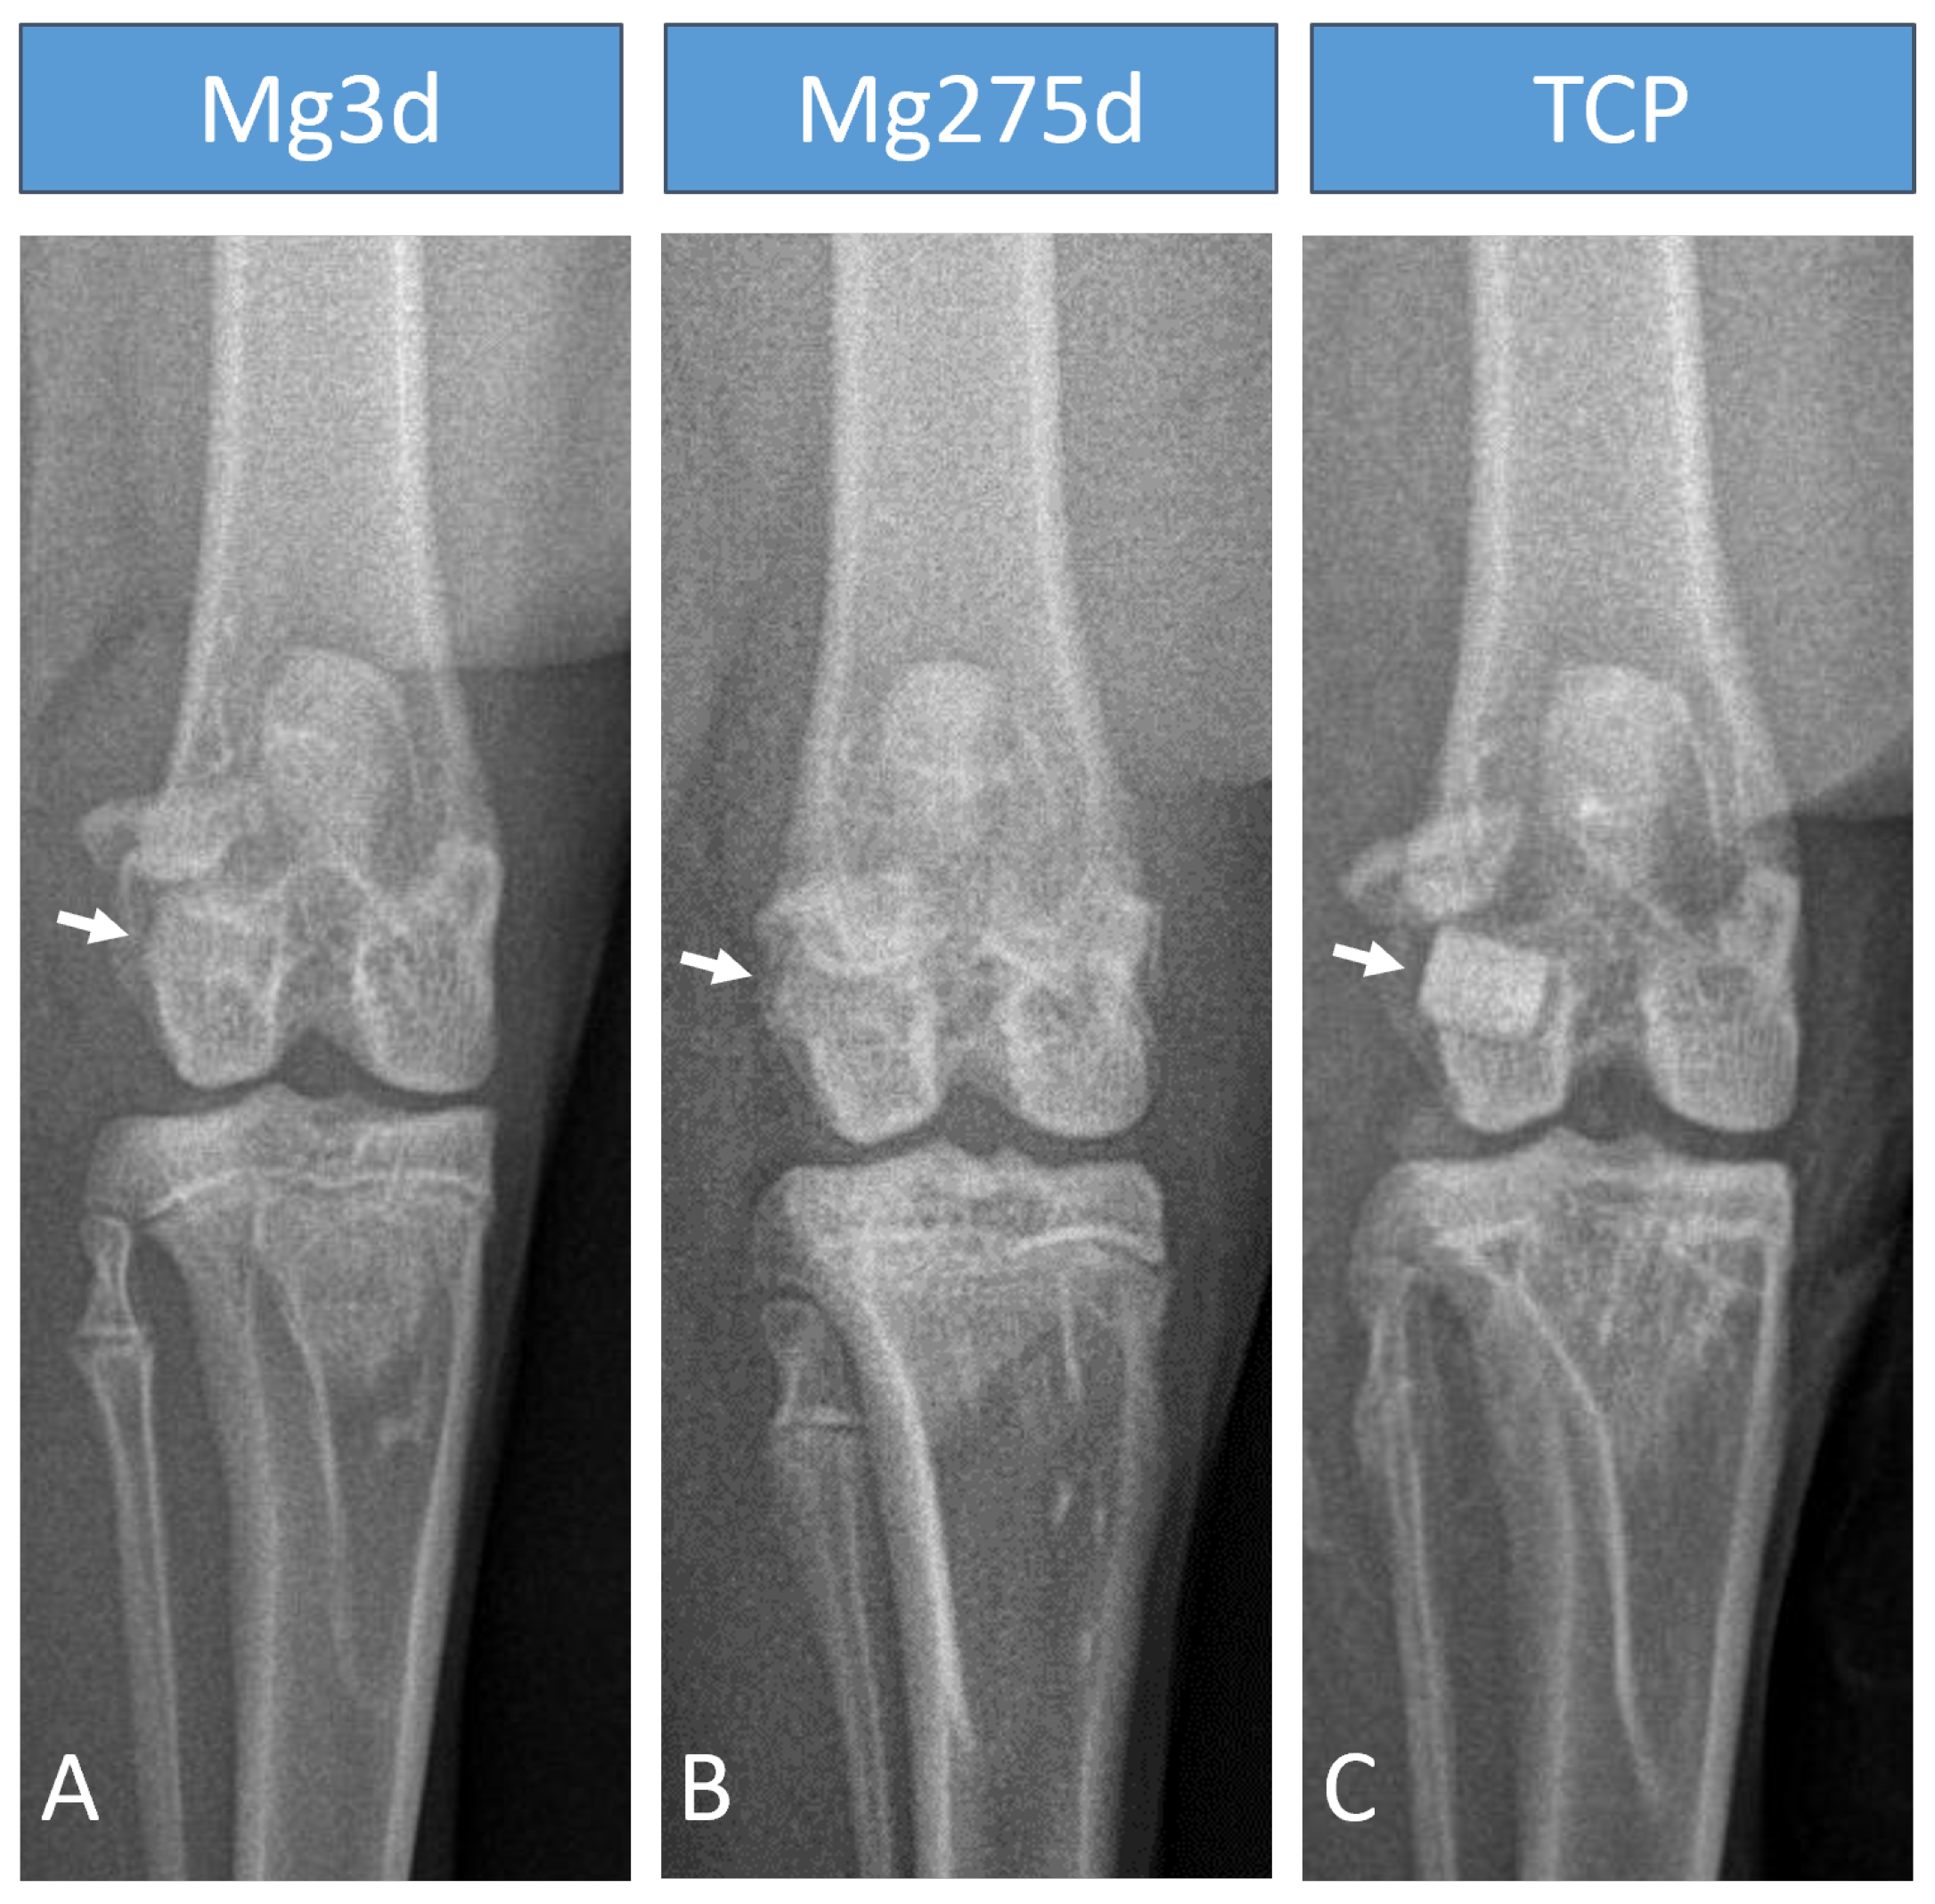

3.3. X-Ray

On the day of the operation, X-ray examination revealed a marked difference in the X-ray density of the three materials. Mg275d and Mg3d had a similar X-ray density to the surrounding bone and were only indistinctly distinguishable (Figure 6A,B). TCP was the most clearly distinguishable material from the surrounding bone (Figure 6C). Immediately after surgery, only 17 of 24 Mg3d scaffolds were visible on the cr/cd images and 19 of 24 on the m/l images. At this point, all scaffolds could be detected in both projections for the other two materials. At the following examination times, the visibility of Mg3d and Mg275d decreased rapidly. By week 4, the number of visible Mg3d and Mg275d scaffolds was significantly lower than that of TCP in both projections (p < 0.001). By week 16, no Mg3d and Mg275d scaffolds were visible on the cr/cd image. At the same time, two of 16 Mg3d scaffolds and one of 16 Mg275d scaffolds were still visible on the m/l image. TCP scaffolds, on the other hand, were clearly visible until the end of the respective examination period.

The X-ray examination immediately after surgery showed that Mg3d and Mg275d had similar radiopacity to the surrounding bone, with Mg3d being the least visible. In contrast, TCP could be clearly distinguished from the surrounding bone due to its high X-ray density [42]. Although this limited long-term radiological monitoring, the rapid loss of visibility indicated accelerated degradation. Similar findings have been reported in other in vivo studies, which also observed reduced visibility and faster degradation of CMPC scaffolds compared to TCP [19,41].